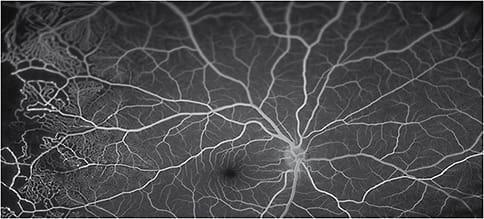

Montaged widefield fluorescein angiogram demonstrating multifocal zones of retinal non-perfusion and vascular leakage secondary to diabetic retinopathy.

Image taken using the 200Tx by Optos